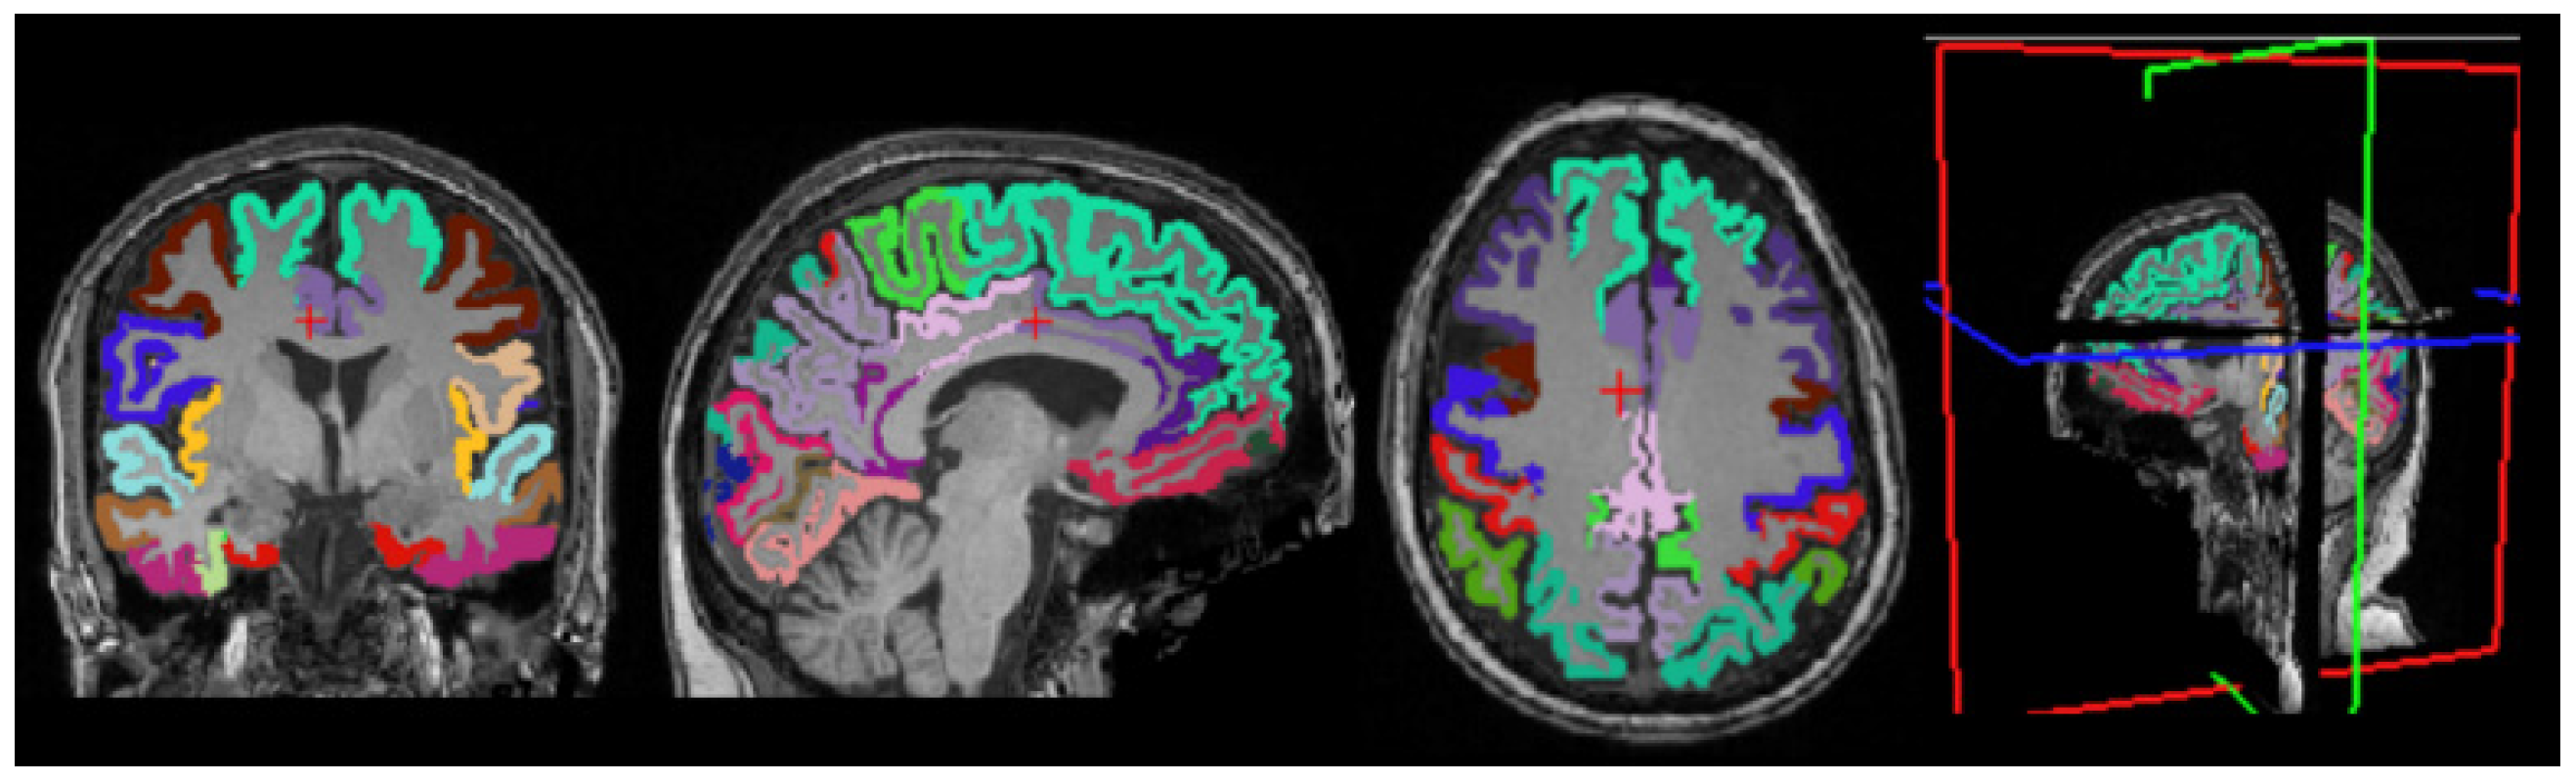

3.4. Cortical Structure Segmentation Results